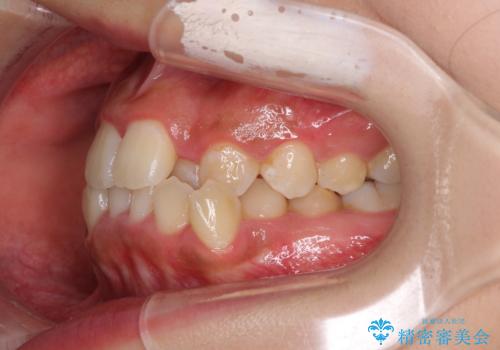

前後に重なった前歯 ワイヤー装置と急速拡大装置を併用したインビザライン矯正

- 前歯の著しい叢生とクロスバイトを気にして来院された患者様です。

叢生が強いため、一見すると抜歯矯正と判断したくなりますが、下顎臼歯が舌側に倒れていることから、上顎骨を側方拡大し、非抜歯矯正の可能性を検討することとしました。

急速拡大装置による上顎骨の側方拡大が思った以上にうまくいき、非抜歯での矯正が可能となりました。

内側に倒れていた下顎の臼歯は起き上がり、清掃性も大幅に改善されました。